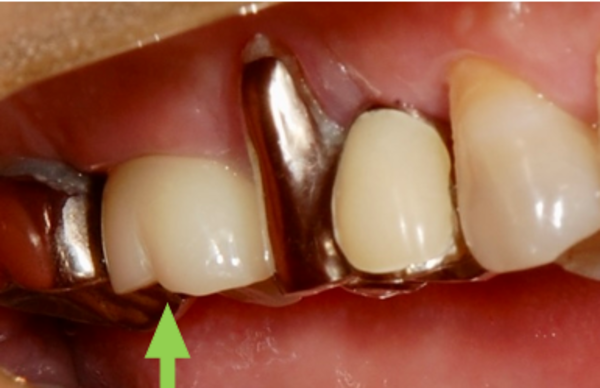

こちらが治療後の歯の写真です。

「膿の臭いがなくなり、しっかり噛めるようになった」と、患者様にもご満足いただけました。